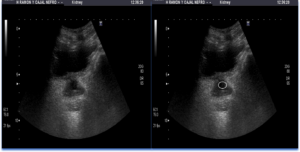

Ecografía Vesicoprostática

La ecografía vesicoprostática se realiza mediante el uso de una herramienta llamada transductor, que envía ondas sonoras de alta frecuencia a través de la piel y los tejidos blandos del abdomen. Las ondas sonoras rebotan en los órganos internos y regresan al transductor, que luego las convierte en imágenes visuales. La ecografía vesicoprostática se utiliza para evaluar la forma, tamaño y estructura de la vejiga y la próstata, así como para evaluar el flujo sanguíneo y la función de estos órganos.